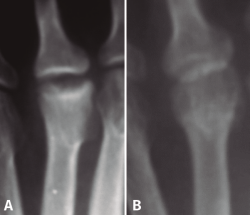

La irrigación de las cabezas de los metatarsianos ha sido estudiada en profundidad por diferentes autores(1,2,3,4,5): depende de las arterias metatarsales dorsales, ramas de la pedia, de las arterias metatarsales plantares, ramas de la arteria tibial posterior, y de la arteria nutricia. Las 2 primeras penetran en la articulación a través de la cápsula, se anastomosan entre sí y forman una arcada arterial de la que salen minúsculos vasos que penetran en la cabeza. Las arterias nutricias atraviesan el córtex del metatarsiano cerca de la inserción de la cápsula y de los ligamentos y van a irrigar el hueso subcondral (Figura 1).

Figura 1. Vascularización de la epífisis distal de los metatarsianos centrales. AMD: arteria metatarsal dorsal; AMP: arteria metatarsal plantar; AN: arteria nutricia; RA: red arterial epifisaria.